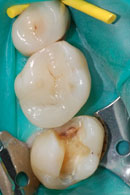

Das Komposit wird anschliessend schichtweise in die Kavität eingebracht und erneut mit Blaulicht ausgehärtet. Dies verhindert die Bildung von Randspalten infolge der unvermeidlichen Polymerisationsschrumpfung des Kunststoffes. Anschliessend erfolgt das Ausarbeiten und Polieren der Füllung.

Aufgrund der oben genannten Schrumpfung sollte man das Legen von zu grossen Kunststoffüllungen vermeiden. Grosse Defekte werden mit laborgefertigten keramischen Inlays versorgt